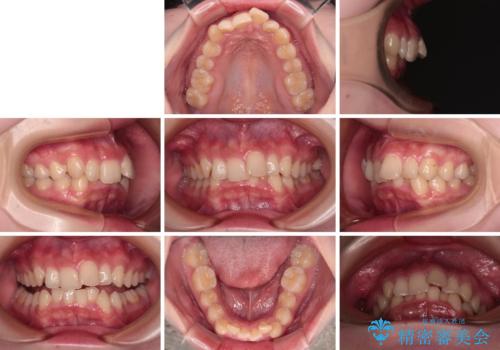

- デコボコになっている前歯を気にして来院された患者様です。

口元の突出感は気になっていないものの、デコボコを解消すると口元が前方に突出する可能性があるため、上下左右の第一小臼歯4本を抜歯して、ワイヤー装置にて矯正治療を行うこととしました。

下の前歯が隠れてしまうほど深く咬みこんでいたため、上顎前歯が前方に突出しているような印象がありましたが、咬み合わせが改善され、整った口元に仕上げることができました。